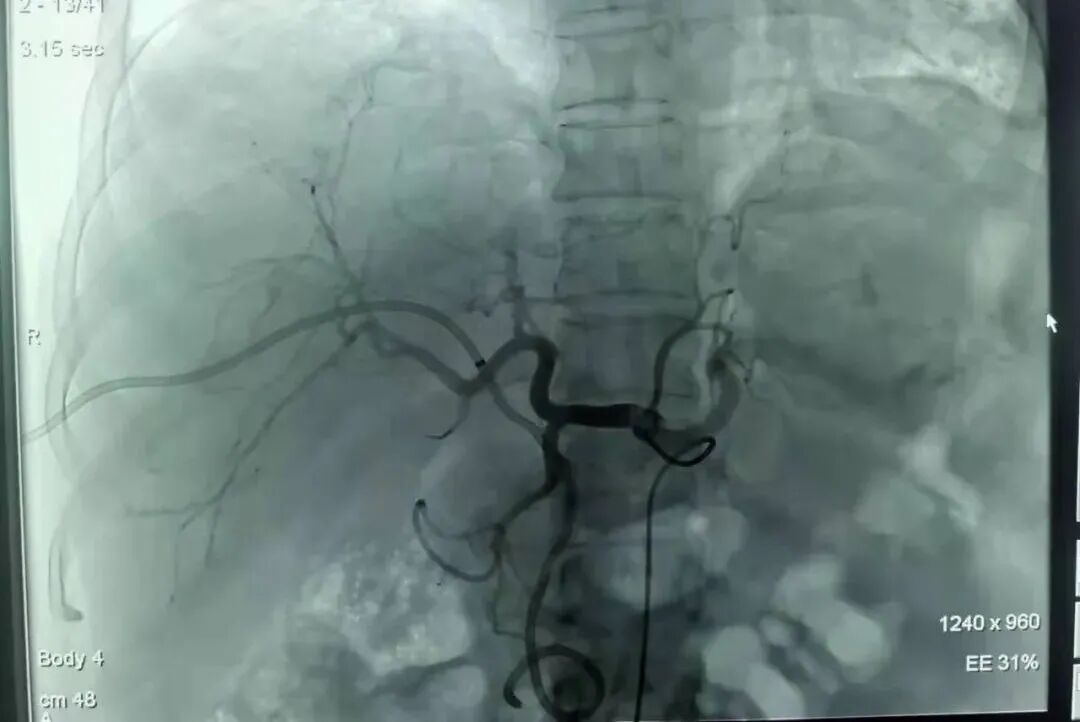

▲图丨左为手术中,右为手术穿刺过程影像

经过充分术前准备,在赵剑波助理的指导下,肿瘤微创介入科为患者实施了PTCD。术中见患者肝内外胆管扩张明显,胆总管下端梗阻,介入手术置入导管侧孔位于梗阻段近端,固定导管,胆汁从导管内顺利引流出来。手术全程不开刀、不出血,患者基本无痛苦,安全返回病房。术后,患者梗阻性黄疸明显好转,复查胆红素降低,患者皮肤、巩膜黄染的情况也明显改善。